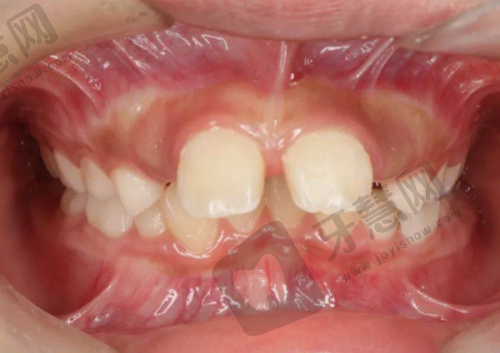

关增辉主事是医院的正畸骨干医生,拥有10余年临床经验,已完成上千例正畸实例。特别擅长儿童早期矫治、成人隐形矫正等高难度病例,是特别多明星和网红的御用正畸医生。

数字化正畸技术更是医院的王牌项目,通过3D口扫获取精细数据,提前预知矫正成效。无论是传统的金属托槽还是高端的隐适美隐形矫正,都能为患者量身定制至佳方案。